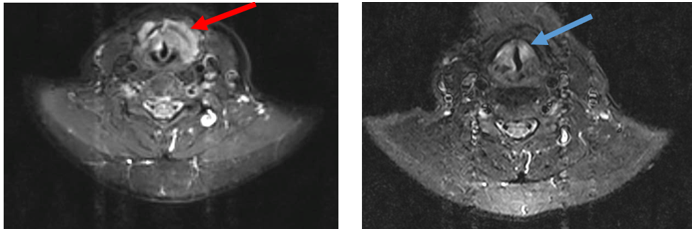

-         MRI vùng cổ (T1/2025)

Hình 1: Khối xâm lấn vùng hạ họng – thanh quản kích thước 41 x 22 mm (mũi tên đỏ), hạch cổ 2 bên, hạch lớn nhất đường kính 10 mm (mũi tên vàng).

Hình ảnh MRI cổ: Hình ảnh tổn thương vùng hạ họng thanh quản giảm kích thước sau điều trị 3 tháng, từ 41 x 22mm (mũi tên đỏ) xuống còn kích thước 20 x 13mm (mũi tên xanh).

Hình ảnh MRI cổ: Hình hạch thượng đòn trái giảm kích thước sau 3 tháng điều trị, từ đường kính 10 mm (mũi tên đỏ) xuống còn 7mm (mũi tên vàng).